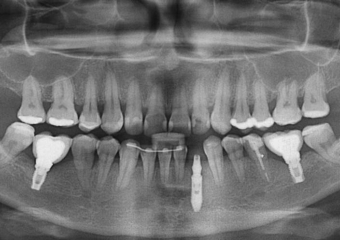

Raio X com próvisório já instalado sobre o implante cone morse